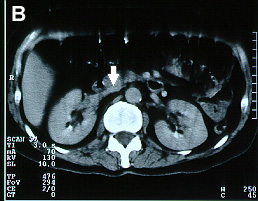

Imagens tomográficas da paciente após a trombose da veia cava inferior. Nota-se a sequência de A para E em que se vê a veia cava normal ao nível das veias renais e abaixo do clipe a veia cava trombosada (aumento do volume com forma circular e halo com captação de contraste)